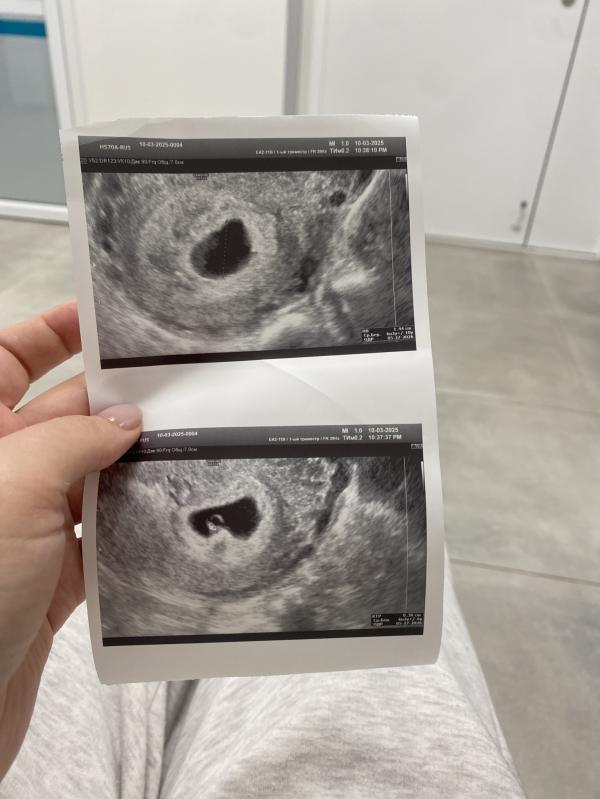

По узи размер соответствует 6,3, была ранняя овуляция. Поэтому рано чувствовать начала)

Сердечко бьется) все замечательно 😍

Подскажите пожалуйста а какой был срок по месячным на этом узи?